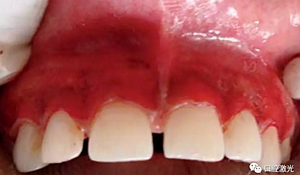

術(shù)后一周

術(shù)后三月